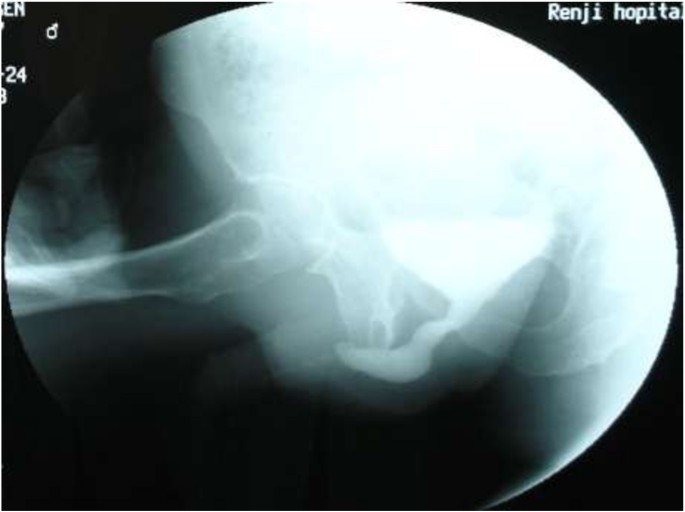

From January 2005 to July 2008, 87 patients (age 9–72 years old; mean 35.6 years old) underwent one-stage dorsal inlay urethroplasty with buccal mucosal graft for anterior urethral stricture. All the cases were performed by a single surgeon (YWJ) and this technique represents standard care at our hospital. The pre-operative assessments included clinical data, urine analysis, uroflowmetry (range from 0.0 ml/s – 13.5 ml/s; mean 5.6 ± 1.5 ml/s), retrograde/voiding cystogram (Figure 1) and urethral ultrasonography to evaluate the degree of scar, and endoscopy to observe the color and luster of urethral mucosa. All-mentioned examination could help to evaluate the degree scar, and the direct observation in surgery is crucial. In cases with severe scar or local infection or poor tissue blood supply, which could affect OMG survival, it is a wise choice to remove the severe scar at the first stage procedure, and convert one-stage to two-stage procedure.